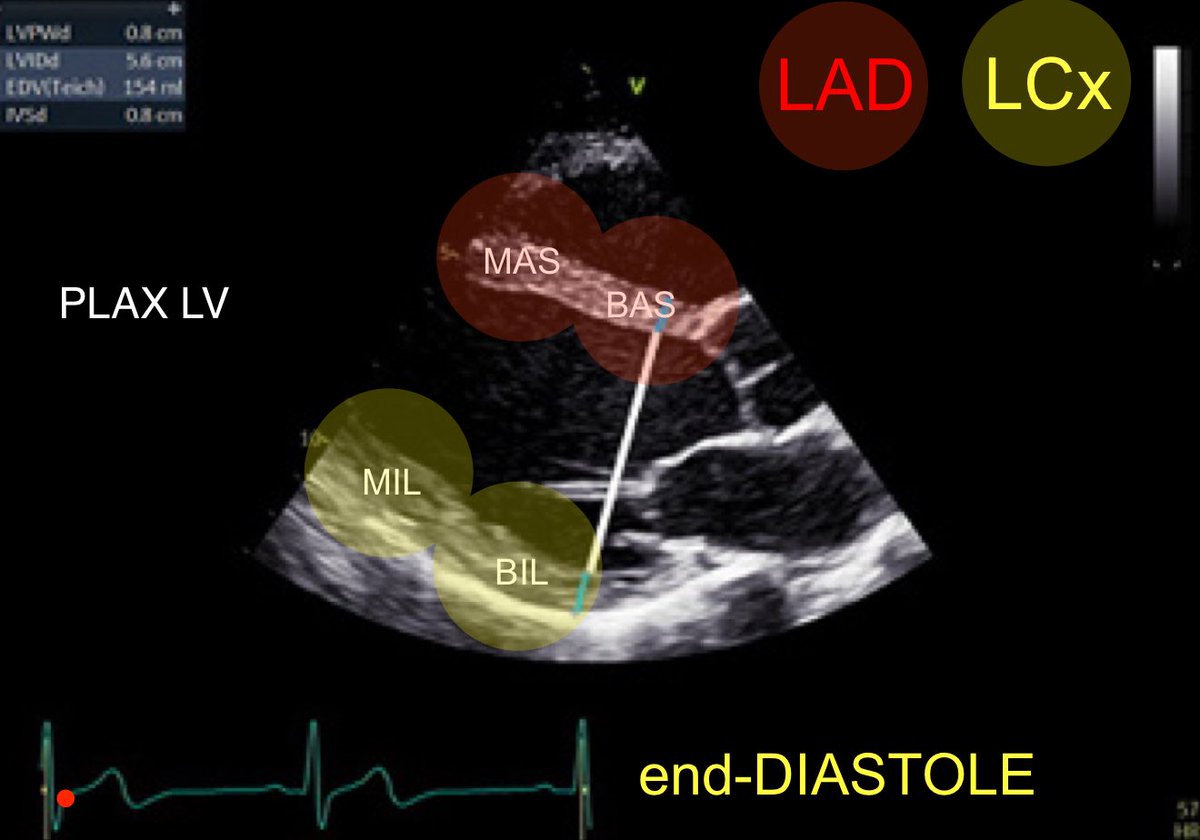

#firstecho #MedEd #POCUS from @BSEcho BAS: Basal antero-septum MAS: Mid antero-septum BIL: Basal infero-lateral MIL: Mid infero-lateral

POCUSpeek's tweet image. #firstecho #MedEd #POCUS from @BSEcho

BAS: Basal antero-septum

MAS: Mid antero-septum

BIL: Basal infero-lateral

MIL: Mid infero-lateral

2 #firstecho #POCUS PLAX view → LV walls with corresponding coronary artery territories Red → LAD Yellow → LCx Source: Transthoracic Echocardiography Foundations of Image Acquisition and Interpretation 3rd Ed (Bernard E. Bulwer)

POCUSpeek's tweet image. 2 #firstecho #POCUS

PLAX view → LV walls with corresponding coronary artery territories

Red → LAD

Yellow → LCx

Source: Transthoracic  Echocardiography  Foundations of Image  Acquisition and Interpretation 3rd Ed (Bernard E. Bulwer)